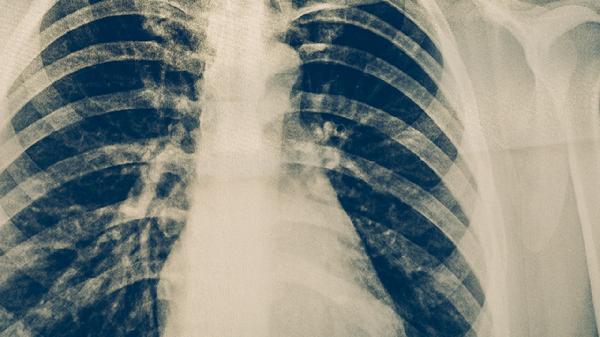

肺結核病是如何傳播的

肺結核病主要通過飛沫傳播、接觸傳播和母嬰傳播三種途徑傳染。肺結核病是由結核分枝桿菌引起的慢性傳染病,主要傳播方式有呼吸道飛沫傳播、密切接觸傳播、母嬰垂直傳播等?;颊呖人浴⒋?a href="http://www.phgsvzt.cn/k/dgiirmiqkreybb9.html" target="_blank">噴嚏或說話時產(chǎn)生的飛沫是主要傳染源,與患者長期密切接觸也可能導致感染,孕婦感染后可能通過胎盤或產(chǎn)道傳染給胎兒。

呼吸道飛沫傳播是肺結核最常見的傳播途徑。當肺結核患者咳嗽、打噴嚏或大聲說話時,會產(chǎn)生含有結核桿菌的飛沫核,這些飛沫核在空氣中懸浮,被健康人吸入后可能導致感染。飛沫傳播的風險與患者排菌量、接觸距離和環(huán)境通風情況有關。在密閉、通風不良的環(huán)境中,飛沫核可長時間懸浮,增加傳播概率。

密切接觸傳播指與活動性肺結核患者長期共同生活或工作,通過直接接觸患者使用的物品或分泌物而感染。結核桿菌可在患者使用過的餐具、衣物等物品表面存活數(shù)小時至數(shù)天,接觸這些污染物后未及時清潔雙手,再觸摸口鼻可能導致感染。免疫功能低下者、兒童和老年人更容易通過接觸傳播感染。

母嬰垂直傳播是較為少見的傳播方式。孕婦患有活動性肺結核時,結核桿菌可能通過胎盤進入胎兒血液循環(huán),或在分娩過程中通過產(chǎn)道感染新生兒。這種傳播方式的發(fā)生概率較低,但可能導致先天性結核病。及時診斷和治療孕婦肺結核可有效預防母嬰傳播。

預防肺結核傳播需采取綜合措施。肺結核患者應佩戴口罩并及時接受規(guī)范治療,健康人群應避免與患者密切接觸,保持室內(nèi)通風良好。接種卡介苗可幫助兒童預防重癥結核病,高危人群應定期進行結核病篩查。如出現(xiàn)持續(xù)咳嗽、低熱、盜汗等疑似癥狀,應及時就醫(yī)檢查。日常生活中注意個人衛(wèi)生,勤洗手,加強營養(yǎng)和鍛煉,提高自身免疫力也有助于預防感染。